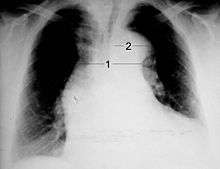

Chest X-ray

Widening of the mediastinum on an X-ray of the chest has moderate sensitivity in the setting of an ascending aortic dissection. However, it has low specificity, as many other conditions can cause a widening of the mediastinum on chest X-ray.

The calcium sign, the separation of the intimal calcification from the outer aortic soft tissue border by 10 mm, is a finding on chest X-ray that suggests aortic dissection.

Pleural effusions may be seen on chest X-ray, more commonly in descending aortic dissections. If seen, they are typically in the left hemithorax.

Other findings include obliteration of the aortic knob, depression of the left mainstem bronchus, loss of the paratracheal stripe, and tracheal deviation.

About 12 to 20% of individuals presenting with an aortic dissection have a "normal" chest X-ray; therefore, a normal chest radiograph does not rule out aortic dissection. If the clinical index of suspicion is high, ruling out dissection with another imaging modality (CT angiogram, MRA, aortogram, or transesophageal echo)is imperative.